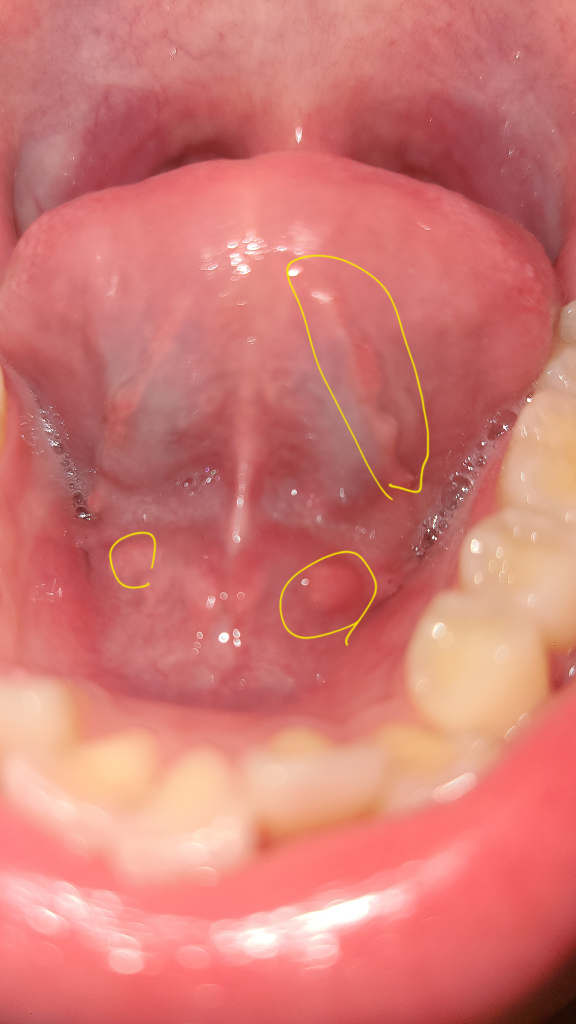

혀 밑에 이것들은 괜찮은 건가요?

오늘 혀 밑을 보니 뭔가 우둘투둘해서요.. 딱히 불편한 느낌은 없는데 정상적인 구조물들인가요?? 혹시 침샘에 문제가 생긴 건 아닌지 여쭙고 싶습니다 ㅠㅠ

• 2번 째 사진

• 안녕하세요. 채홍석 의사입니다. 혀 아래쪽에는 원래 울퉁불퉁한 부분이 있습니다. 침샘입구 혹은 혈관등이 지나가기 때문입니다.

정상적인 구조물이고 염증 등의 이상소견이 보이지 않습니다. 불편감이 없으시다면 그냥 지내셔도 괜찮습니다.